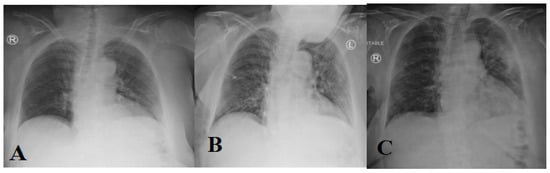

A chest radiograph (X-ray) is the common way to diagnose patients with respiratory diseases. A chest X-ray image can be viewed as normal at the early stages, but it gradually changed in a way that may correlate with other respiratory diseases such as pneumonia or acute respiratory distress syndrome (ARDS). Two common changes that arise in the COVID-19-infected lung include (1) accumulation of tissue or fluid in a way that prevents gas exchange; and (2) the appearance of nodular shadowing. Figure 5 shows the progression of X-ray images for a 45-year-old patient.

Figure 5.

(A–F) subfigures show progression of an X-ray image for a COVID-19 patient across days (1, 3, 6, 7, 8, and 10, respectively).